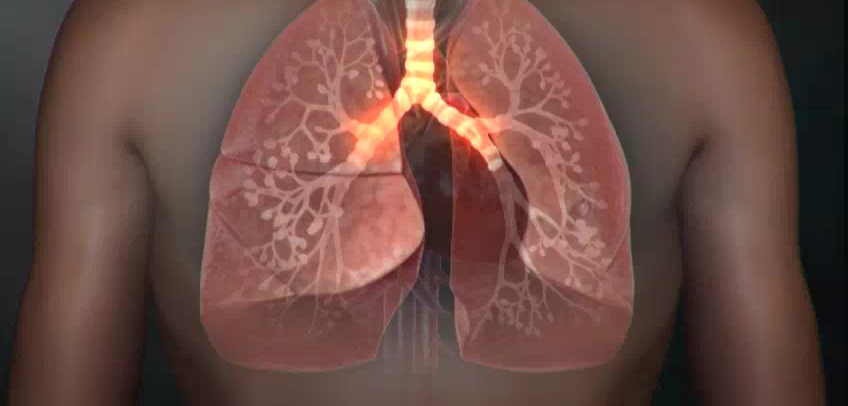

폐렴 증상 10. 빠른 심박수(빈맥)

- 산소 공급이 줄어들면 심장이 더 빨리 뛰어 보충하려 함

- 안정 시에도 심박수가 빨라지고, 가슴 두근거림이 심해짐